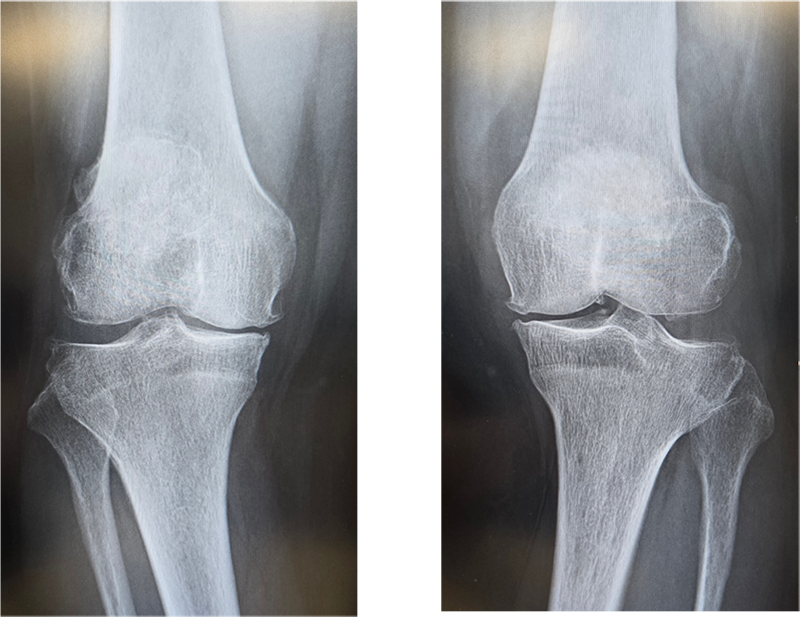

変形性膝関節症は一次性と原因疾患に続発する二次性に分類されます。わが国では年齢による退行性変化を主因とする一次性が多く、軟骨のすり減り、骨棘(骨のとげ)を伴い、多くは内反変形(O脚)を呈します。女性に多く、特に肥満との関連が強いといわれています。膝関節には歩行するだけで体重の3倍の力がかかるといわれており、病状の予防や進行を抑えるためには体重のコントロールが最も重要です。症状には波がありますが、次第に進行し、変形も悪化してきます。まずは保存加療を行いますが、痛みが強く日常生活に支障をきたすようだと、我慢するメリットはありません。痛みのない脚でより良い人生を送るために手術という選択肢もありますので、痛みで悩まれている場合は早めにご相談ください。

〈手術前のレントゲン〉